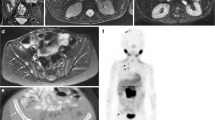

Diffusion-weighted MR imaging (DWI-MRI) has been used clinically for many years, primarily in neuroradiology where the use of diffusion imaging dramatically changed our ability to image cerebral ischemia and identify patients who would be amenable to early treatment intervention with thrombolytics and anticoagulents. With the development of faster scanning techniques, it has now become possible to routinely perform DWI in the abdomen. DW-MRI has emerged as a potential novel biomarker in oncological imaging, where it has been linked to lesion aggressiveness and tumor response [36, 37]. A recent report from the National Cancer Institute emphasized the importance of DW-MRI as a cancer biomarker and provided a consensus panel’s recommendations for how to validate and incorporate DWI into oncological imaging protocols [36]. DW-MRI relies on imaging the microscopic mobility of water. This mobility, known as Brownian motion, is highly influenced by the microenvironment around the water. For example, impaired water movement in and out of cells due to ischemia manifests as restricted diffusion. Similarly, highly ordered tissues are expected to have more restricted free water diffusivity as compared to free fluid, or to tissues with limited or no cellularity. As with most tissues examined using MR imaging, individual diffusion measurements for individual tissues differ [38]. However, in general, it has been recognized that cellular tumors typically manifest restricted diffusivity to a degree greater than the surrounding tissues, allowing for increased lesion conspicuity. DW-MRI has the advantage of not requiring intravenous contrast agents, and small cellular lesions can be detected with exquisite sensitivity using DW-MRI, often when they are below the limits of detection with other techniques (Fig. 3). Furthermore, changes in the tumor in response to therapy, such as tumor necrosis, can be expected to decrease cellular density and increase intra- and extracellular free water, resulting in changes in diffusivity in response to therapy. This underscores the two main uses for which DWI in oncology has been incorporated: improved lesion detection and assessment of response to therapy.

Fat-suppressed T2-W MRI, DW-MRI, CT and fused PET/CT images in a patient with adrenal cortical carcinoma show intense FDG uptake and restricted diffusivity in the large metastatic liver lesions in the right liver lobe. The tiny lesion in the left lateral segment of the liver (arrow) is clearly detectable on the diffusion-weighted MR images (DWI), but is inconspicuous or undetectable with the other images sequences and techniques, emphasizing the role that DW-MRI plays in improving sensitivity for lesion detection

As a biomarker for the quantitative evaluation of tumor response to therapy, DWI is especially appealing as a means of quantifying the diffusivity of water molecules within a tumor. The Apparent Diffusion Coefficient (ADC) map is used to measure the actual diffusivity of the tissue. Changes in the ADC values are inversely correlated with tumor cellularity and are used to evaluate the tumor’s response to therapy [38]. Current techniques use the mean or median ADC value of an ROI within the tumor to quantify the tumor response. However, we have found the response of ADC to therapy in the clinical setting to be more complex to quantify due to inherent pretreatment and post-treatment heterogeneity observed within human tumors (Fig. 4) and use of ADC response will require development of advanced measurements to quantify the tumor response throughout the entire tumor volume with greater accuracy. It must be said that the physical basis for why malignant tumors have lower ADC values is not completely understood, but probably relates to a combination of inherent increased cellularity and tissue disorganization, resulting in reduced motion of free water within the tumor [36]. More work will be needed during the coming years to determine which tumors can be expected to show restricted diffusion on routine imaging sequences. Furthermore, how tumors will respond to therapy and how these changes in diffusivity are reflected in patient outcome remain to be determined for the majority of pediatric solid tumors.

Diffusion-weighted (b = 400) and fat-suppressed T2-W MR images are shown together with the calculated ADC map in a patient with neuroblastoma. The left pedicle lesion in the vertebral body is easily seen on the DW-MR images (arrow), as well as the patient’s primary tumor. The ADC map confirms restricted diffusivity throughout the tumor. The histograms demonstrate the composite of ADC values calculated throughout the entire tumor volume and emphasize both the heterogeneity of the tumor ADC values, and value of such an analysis in measuring quantitative changes in the tumor during therapy: compare the pre- and post- histograms, showing a global increase in ADC following therapy, reflecting an increase in diffusivity, possibly related to tumor necrosis, decreased tumor cellularity or both

Equally important is the potential ability for DWI-MRI to distinguish between benign and malignant lesions. There are several studies showing that the apparent diffusion constant (a calculated value which reflects actual tumor diffusivity, accounting for background signal due to inherent T2 properties of the tissue and blood flow/perfusion effects) can be used to help distinguish between benign and malignant lesions [38]. As shown in Fig. 3, DWI can afford exquisitely sensitive lesion detection and increased conspicuity of lesions that aren’t otherwise apparent on both conventional T2 and post-gadolinium enhanced MR images. Furthermore, changes in tumor diffusivity can be seen even when tumor shrinkage has not yet occurred. It has been suggested that DW-MRI may be an effective early biomarker for treatment outcome for drugs that disrupt the vasculature and induce apoptosis, since cellular death and vascular changes, which can be reflected in changes in diffusivity, frequently precede changes in lesion size [36]. Preclinical work has shown that DWI can distinguish between nonperfused viable and nonperfused necrotic tissue. In several early clinical trials, rising ADC values (reflecting increasing diffusivity within the tumor, presumably related to necrosis) were shown in response to therapy in both primary and metastatic tumors. A corollary to this is the absence of a significant change in tumor size or an increase in size coupled with a persistently low ADC (highly restricted diffusivity) may add additional evidence supporting a lack of tumor response to therapy. It is likely that changes in ADC will also reflect tissue dehydration and fibrosis, in addition to tumor necrosis, and the resultant overall change in ADC will probably be a complex mix of biophysical processes. This will require a systematic approach to assessing and correlating ADC values with tissue biopsy when possible and with ultimate patient outcome. This correlation will determine whether monitoring changes in diffusivity will be a reasonable correlate for response and whether it indeed has prognostic significance in distinguishing satisfactory to poor patient outcome [39].